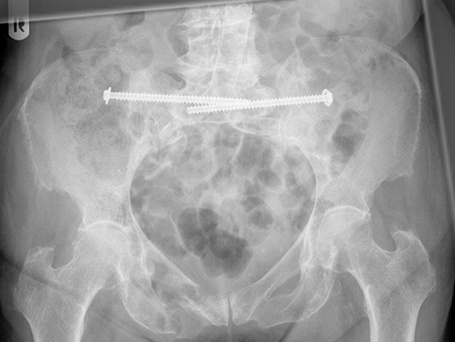

89-jährige Patientin mit Beckenringfraktur beidseits transsacral und rechtsseitigem vorderen Schambein und Sitzbeinbruch. Auch im Nachhinein konnte anhand der zuerst auswärtig erstellten Röntgenbilder kein Bruch erkannt werden. Bei der ersten Vorstellung hier 4 Wochen nach dem Unfall zeigten die Kontrollbilder dann eindeutig die Verletzung und wir veranlassten eine CT Untersuchung. Bei den Beckenbrüchen der alten Patient*innen kann in vielen Fällen ohne Operation behandelt werden. Bei anhaltenden Schmerzen sollte jedoch erneut Diagnostik erfolgen und dann gegebenenfalls auch eine operative Stabilisation durchgeführt werden, um eine chronische Fraktur und die damit verbundenen Schmerzen und Immobilität zu vermeiden.

Es wurde bei der Patientin eine Verschraubung des Beckens durchgeführt und damit die Situation so stabilisiert, dass die Patientin wieder mobilisiert werden konnte.

OPERATIVE VERSORGUNG DER PATIENTIN

Beiderseitige Sacrumfraktur

Beckenringfraktur post-operativ

Beckenringfraktur Verschraubung